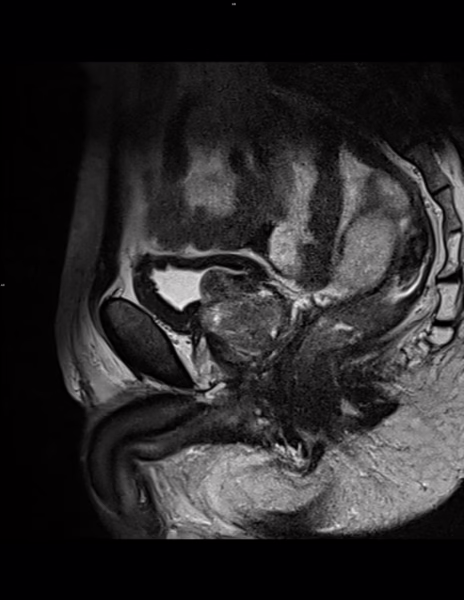

Tamaño de la próstata: 56 mm transverso x 36 mm AP x 4.7 mm de longitud con volumen total de: 50 cm³. Longitud de la uretra membranosa de 10 mm. Ápice tipo A.

Se observan cambios por hipertrofia prostática con patrón de crecimiento tipo III (transicional bilateral y retroureteral), con protrusión del lóbulo medio hacia el piso vesical en 12 mm (IPP grado 3).

Se favorece engrosamiento de la pared vesical en relación con cambios por vejiga de esfuerzo (mide 8.4 mm de AP).

Vesículas seminales: simétricas, distendidas, sin alteraciones.

Hallazgos compatibles con Hiperplasia Prostática con IPP grado 3 y volumen total de 50 cm³.

Cambios por vejiga de esfuerzo.